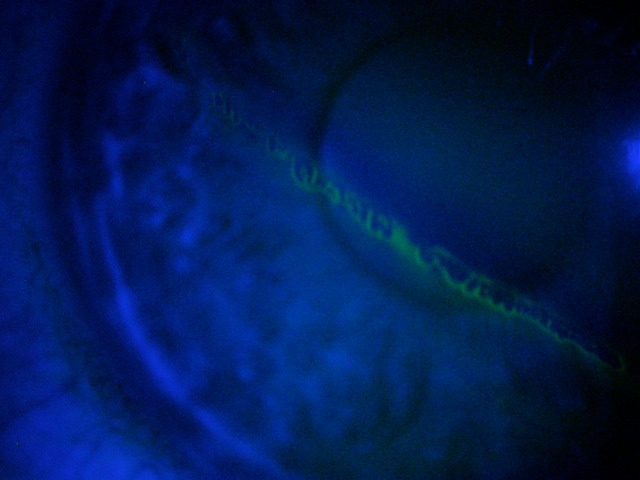

Corneal abrasion